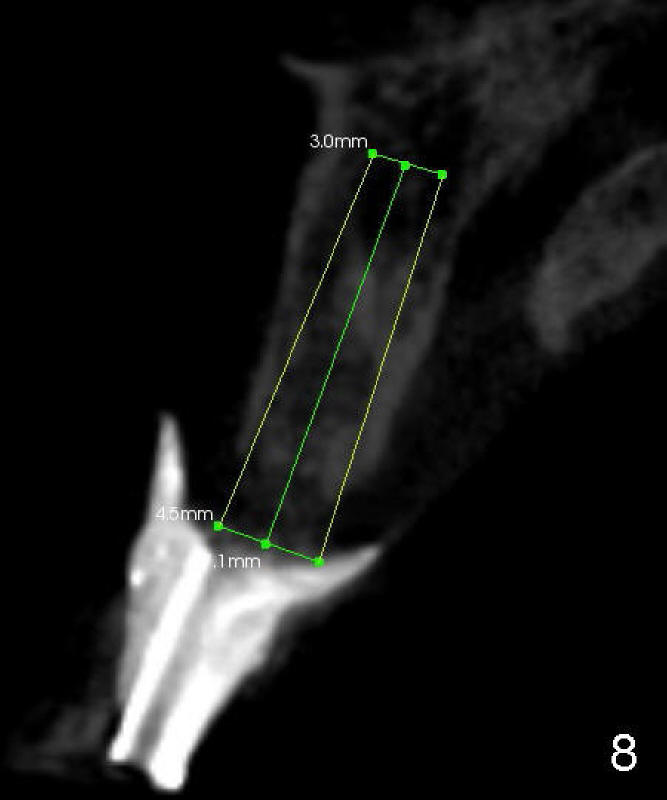

CBCT with surgical stent shows that it is possible to place 4x17 and 4.5x17 tapered implants for the sites #7 and 8 with bone expansion, respectively (Fig.5 coronal section, Fig.6 axial (at the level of 16.4 mm line in Fig.5), Fig.7, 8 sagittal across the site #7 and 8, respectively).